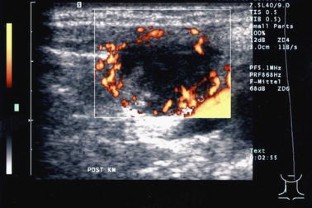

In 55 patients, 40 lymph nodes were correctly categorized as benign and 15 lymph nodes correctly as malignant. The most reliable criteria were shape and vascularization pattern. Intact hilar vessels and branching indicated benign enlargement, destruction of the hilum with vessels running peripherally along the capsule indicated metastatic destruction. Two benign lymph nodes were considered malignant (false positive).

Abb. 1